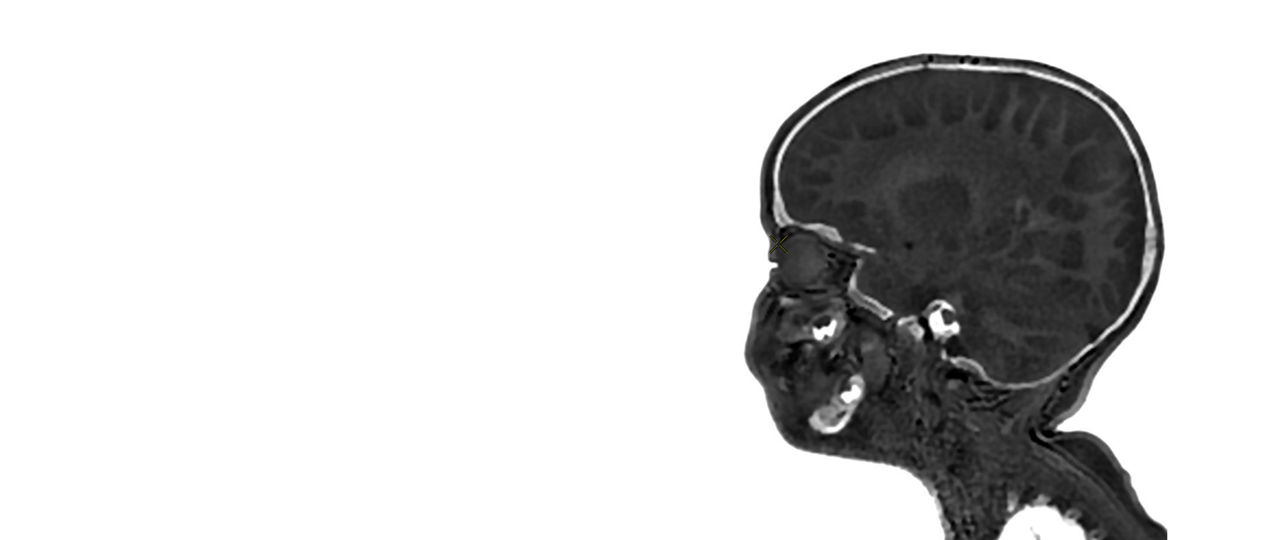

Pediatric MRI for SIGNA

Specialized pediatric MRI protocols specifically designed to meet the needs of your smallest, most fragile patients. Provide ease of use for technologists and clinical excellence for clinicians.